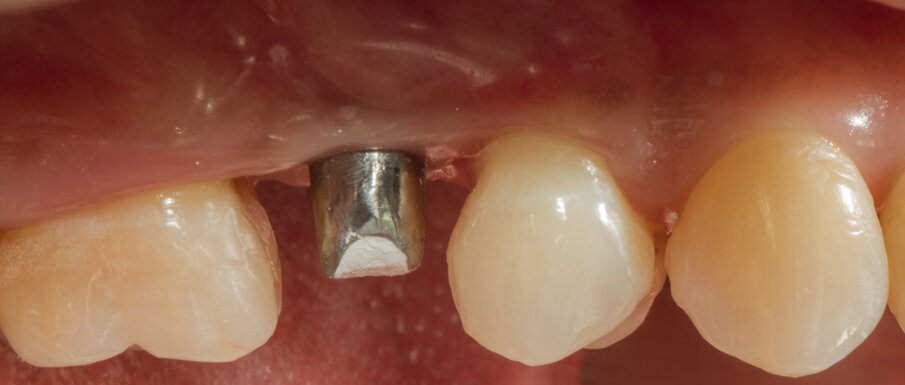

Caso clinico Viene presentato un caso clinico di GBR per la ricostruzione volumetrica di una cresta ossea atrofica mascellare con inserimento di biomateriale osseo di natura eterologa (OsteoBiol Gen-Os) e di una lamina corticale soft collagenata (OsteoBiol Lamina Soft) stabilizzata sulla sede del difetto osseo con utilizzo di colla di fibrina (Tisseel, Baxter) e con 2 chiodini di fissazione crestali. La paziente N.H. di anni 42, sesso femminile, non fumatrice, ASA 1, si presentò alla mia osservazione per la sostituzione di un elemento dentale, 2° premolare superiore destro, estratto più di 15 anni prima (Figg. 2, 3). Dall’esame clinico si osserva un marcato riassorbimento in senso orizzontale del sito edentulo, lo stato dei tessuti gengivali è di salute, non vi sono lesioni parodontali sui denti contigui. L’esame CBCT conferma la perdita di oltre il 50% del tessuto osseo vestibolare pur rimanendo conservata l’altezza verticale della cresta (Fig. 4).

Fig. 2 - Situazione iniziale.

Dopo aver passivizzato il lembo si esegue una sutura a materassaio orizzontale e punto staccato centrale sulla parte crestale e suture semplici sulle incisioni di scarico (Figg. 13, 14). Dopo 10 mesi di guarigione si può procedere all’intervento di posizionamento implantare (Figg. 15-17). Sia dalle fotografie a lembo aperto (Figg. 18, 19) e da quelle di confronto tra la situazione alla baseline e dopo rigenerazione della cresta ossea (Figg. 20, 21) si può valutare come si sia ricostituito un osso ben corticalizzato, vascolarizzato, che ha riempito tutto il difetto osseo preesistente.

Viene inserito nel centro della cresta neoformata un impianto osteointegrato Neoss Tapered 4.0 x 13 mm con torque di inserimento di 60 Ncm e ISQ 80 (Figg. 22-24). La rigenerazione ossea crestale permette di inserire l’impianto in una posizione protesicamente guidata e con 2 mm di tessuto osseo vestibolare; questa situazione migliora la prevedibilità della riabilitazione implanto-protesica29-33. Dopo 2 mesi di provvisorizzazione si cementa il manufatto protesico definitivo (Figg. 25-28). Il controllo clinico e radiologico a 6 anni (Figg. 29, 30) mostra la stabilità dei tessuti molli e dell’osso perimplantare. Il confronto tra baseline e 6 anni dalla riabilitazione protesica evidenzia la stabilità nel tempo della rigenerazione volumetrica crestale (Fig. 31).

Fig. 25 - Situazione tissutale dopo 2 mesi di provvisorizzazione.